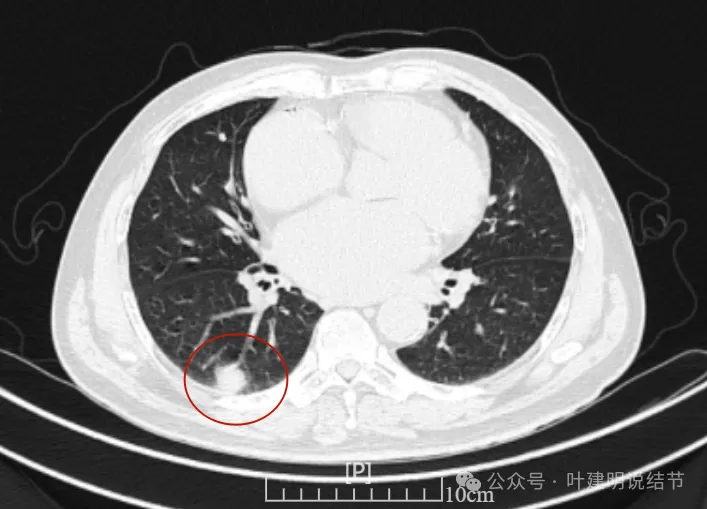

再看2022年8月复查时AI报告找出来的影像:

多是微小实性结节,主要的仍是右上与左下的这两处,较3月时无明显变化。而右下原来似有微小结节处这次并不明显。